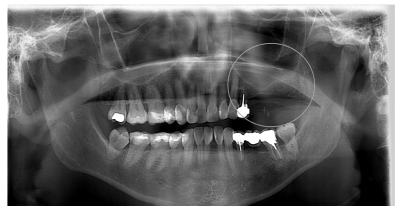

Tras estos hallazgos se aconsejó a la paciente la extracción del 26 conservando el 24. Una vez obtenido el consentimiento informado se procedió al corte de la prótesis, a nivel del 24 y posterior extracción del 26, sin complicaciones. Transcurridos cinco meses se volvió a solicitar un control radiográfico, en el que se observó la correcta remodelación de la zona, así como el déficit óseo para la rehabilitación con implantes (Figura 2).

Tres meses más tarde, la paciente acudió de nuevo a la consulta con la finalidad de rehabilitar las ausencias de 25, 26 y 27, solicitándose un estudio mediante CBCT, en el que se observó una altura de1,63 mm y 11,6 mm de anchura (Figura 3).